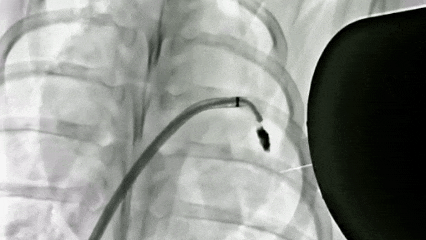

数字减影血管造影(DSA)拍摄的巴马猪体内磁流体左心耳封堵实验过程。深圳先进院供图

研究采用介入手术将磁流体注入猪左心耳,借助机械臂控制磁铁提供抗血流磁力,20分钟后磁流体形成磁凝胶,手术全程无磁流体泄漏。